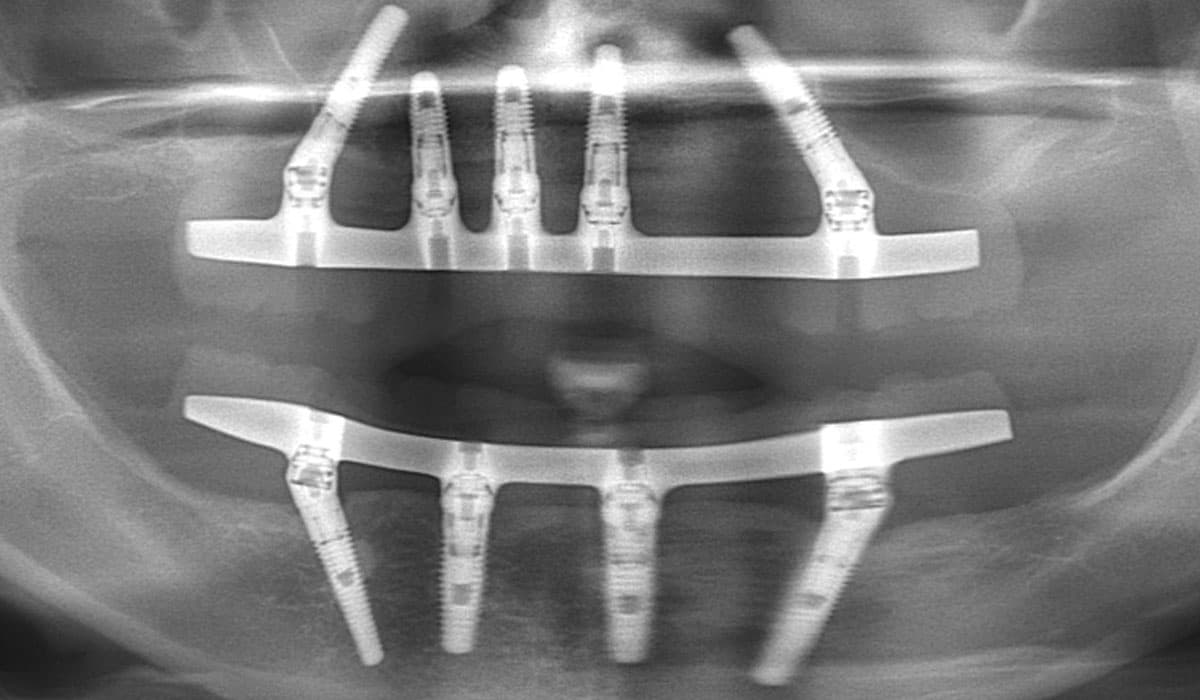

Receive a complete set of permanent teeth in a single visit with our All-on-4 and All-on-6 immediate-load implant protocols. Dr. Antipov uses 3D cone beam CT imaging and computer-guided surgical templates for precise, predictable placement — even for patients who have been told they don't have enough bone. For severe upper jaw bone loss, we offer zygomatic implants anchored to the cheekbone, eliminating the need for extensive bone grafting. Every full arch case includes same-day temporary teeth so you never leave without a smile.

Same-Day Teeth — Walk Out Smiling

Using the All-on-4 and All-on-6 immediate-loading protocols, Dr. Antipov places dental implants and attaches a full set of temporary teeth in a single visit. You arrive with missing or failing teeth and leave the same day with a complete, natural-looking smile. No waiting months without teeth.